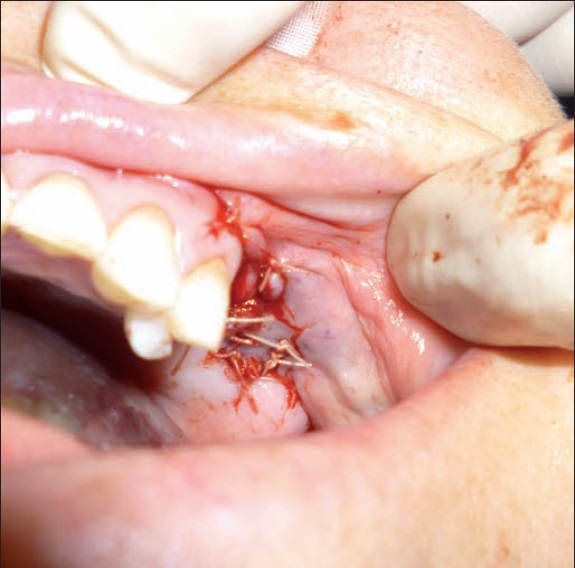

La paciente fue sometida a cirugía con mucosectomía del seno maxilar mediante abordaje de Cadwell-Luc, y cierre de la fístula con un colgado mucoperióstico vestibular de avance ( Fig. 3 y 4). Además, en el mismo acto operatorio, llevamos a cabo via abordaje vestibular inferior, incisión de la mucosa alveolar, desbridamiento del foco de osteonecrosis mandibular y cierre con colgajo local.

A las 3 semanas de postoperatorio la paciente presentaba cierre de la fístula oroantral sin dehiscencia o necrosis del colgajo, con resolución de los síntomas de presentación, a saber: dolor, paso de líquidos al seno maxilar y halitosis. En el seguimiento a 6 meses de postoperatorio ( Fig. 5), comprobamos la ausencia de recidivas y la mejoría en la calidad de vida de la paciente.